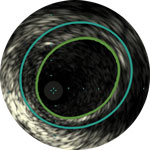

Behandlungsplan Beispiel 2

Lumen mit frischem Thrombus

Mikrokalzifizierung

Kalzifizierte Plaque mit Schallschatten

Gefässgrösse: 6 mm Durchmesser Plaquemorphologie: gemischte, thrombotische Plaque mit mittlerem Calcium Plaquegeometrie: exzentrische Läsion Position des Führungsdrahtes: wahres Lumen

Quick-Cross-Katheter: souverän komplexe Morphologien durchqueren Turbo-Power-Laser-Atherektomie: vorwärts gerichtetes, direktionales Abtragen zur Beseitigung von Thromben; Rotation für verbessertes Abtragen in kalzifizierten Läsionen AngioSculpt Scoring-Ballonkatheter: sicheres Aufweiten von Reststenosen4 Stellarex DCB: entwickelt für hohe Leistungsfähigkeit bei Kalfizifierungen